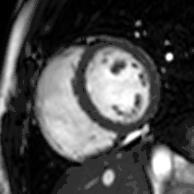

Late gadolinium enhancement

Gadolinium-based contrast agents are administered intravenously and delayed imaging is performed at least 10 minutes later to achieve optimum contrast between normal and infarcted myocardium. An inversion recovery (IR) sequence is used to null the signal from normal myocardium. Myocardial viability can be assessed by the degree of transmural enhancement. Cardiomyopathic, inflammatory and infiltrative diseases may also have distinctive patterns of non-ischemic LGE.[21][22]